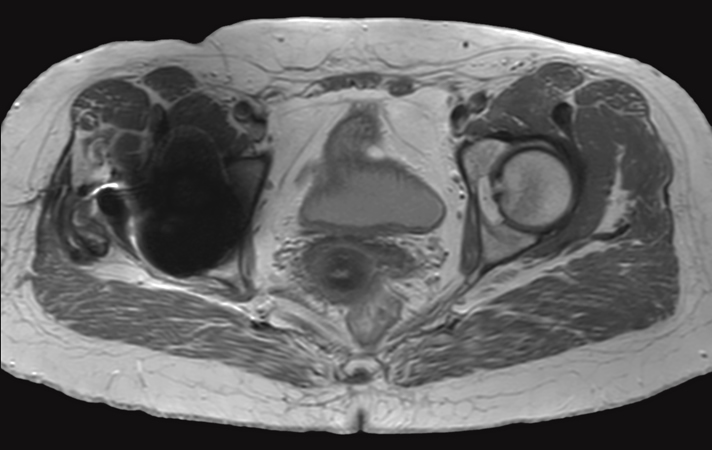

Hip imaging with metal implant

Used Solution

**Only for use with MR Safe or MR Conditional Implants by strictly following the Instructions for Use.